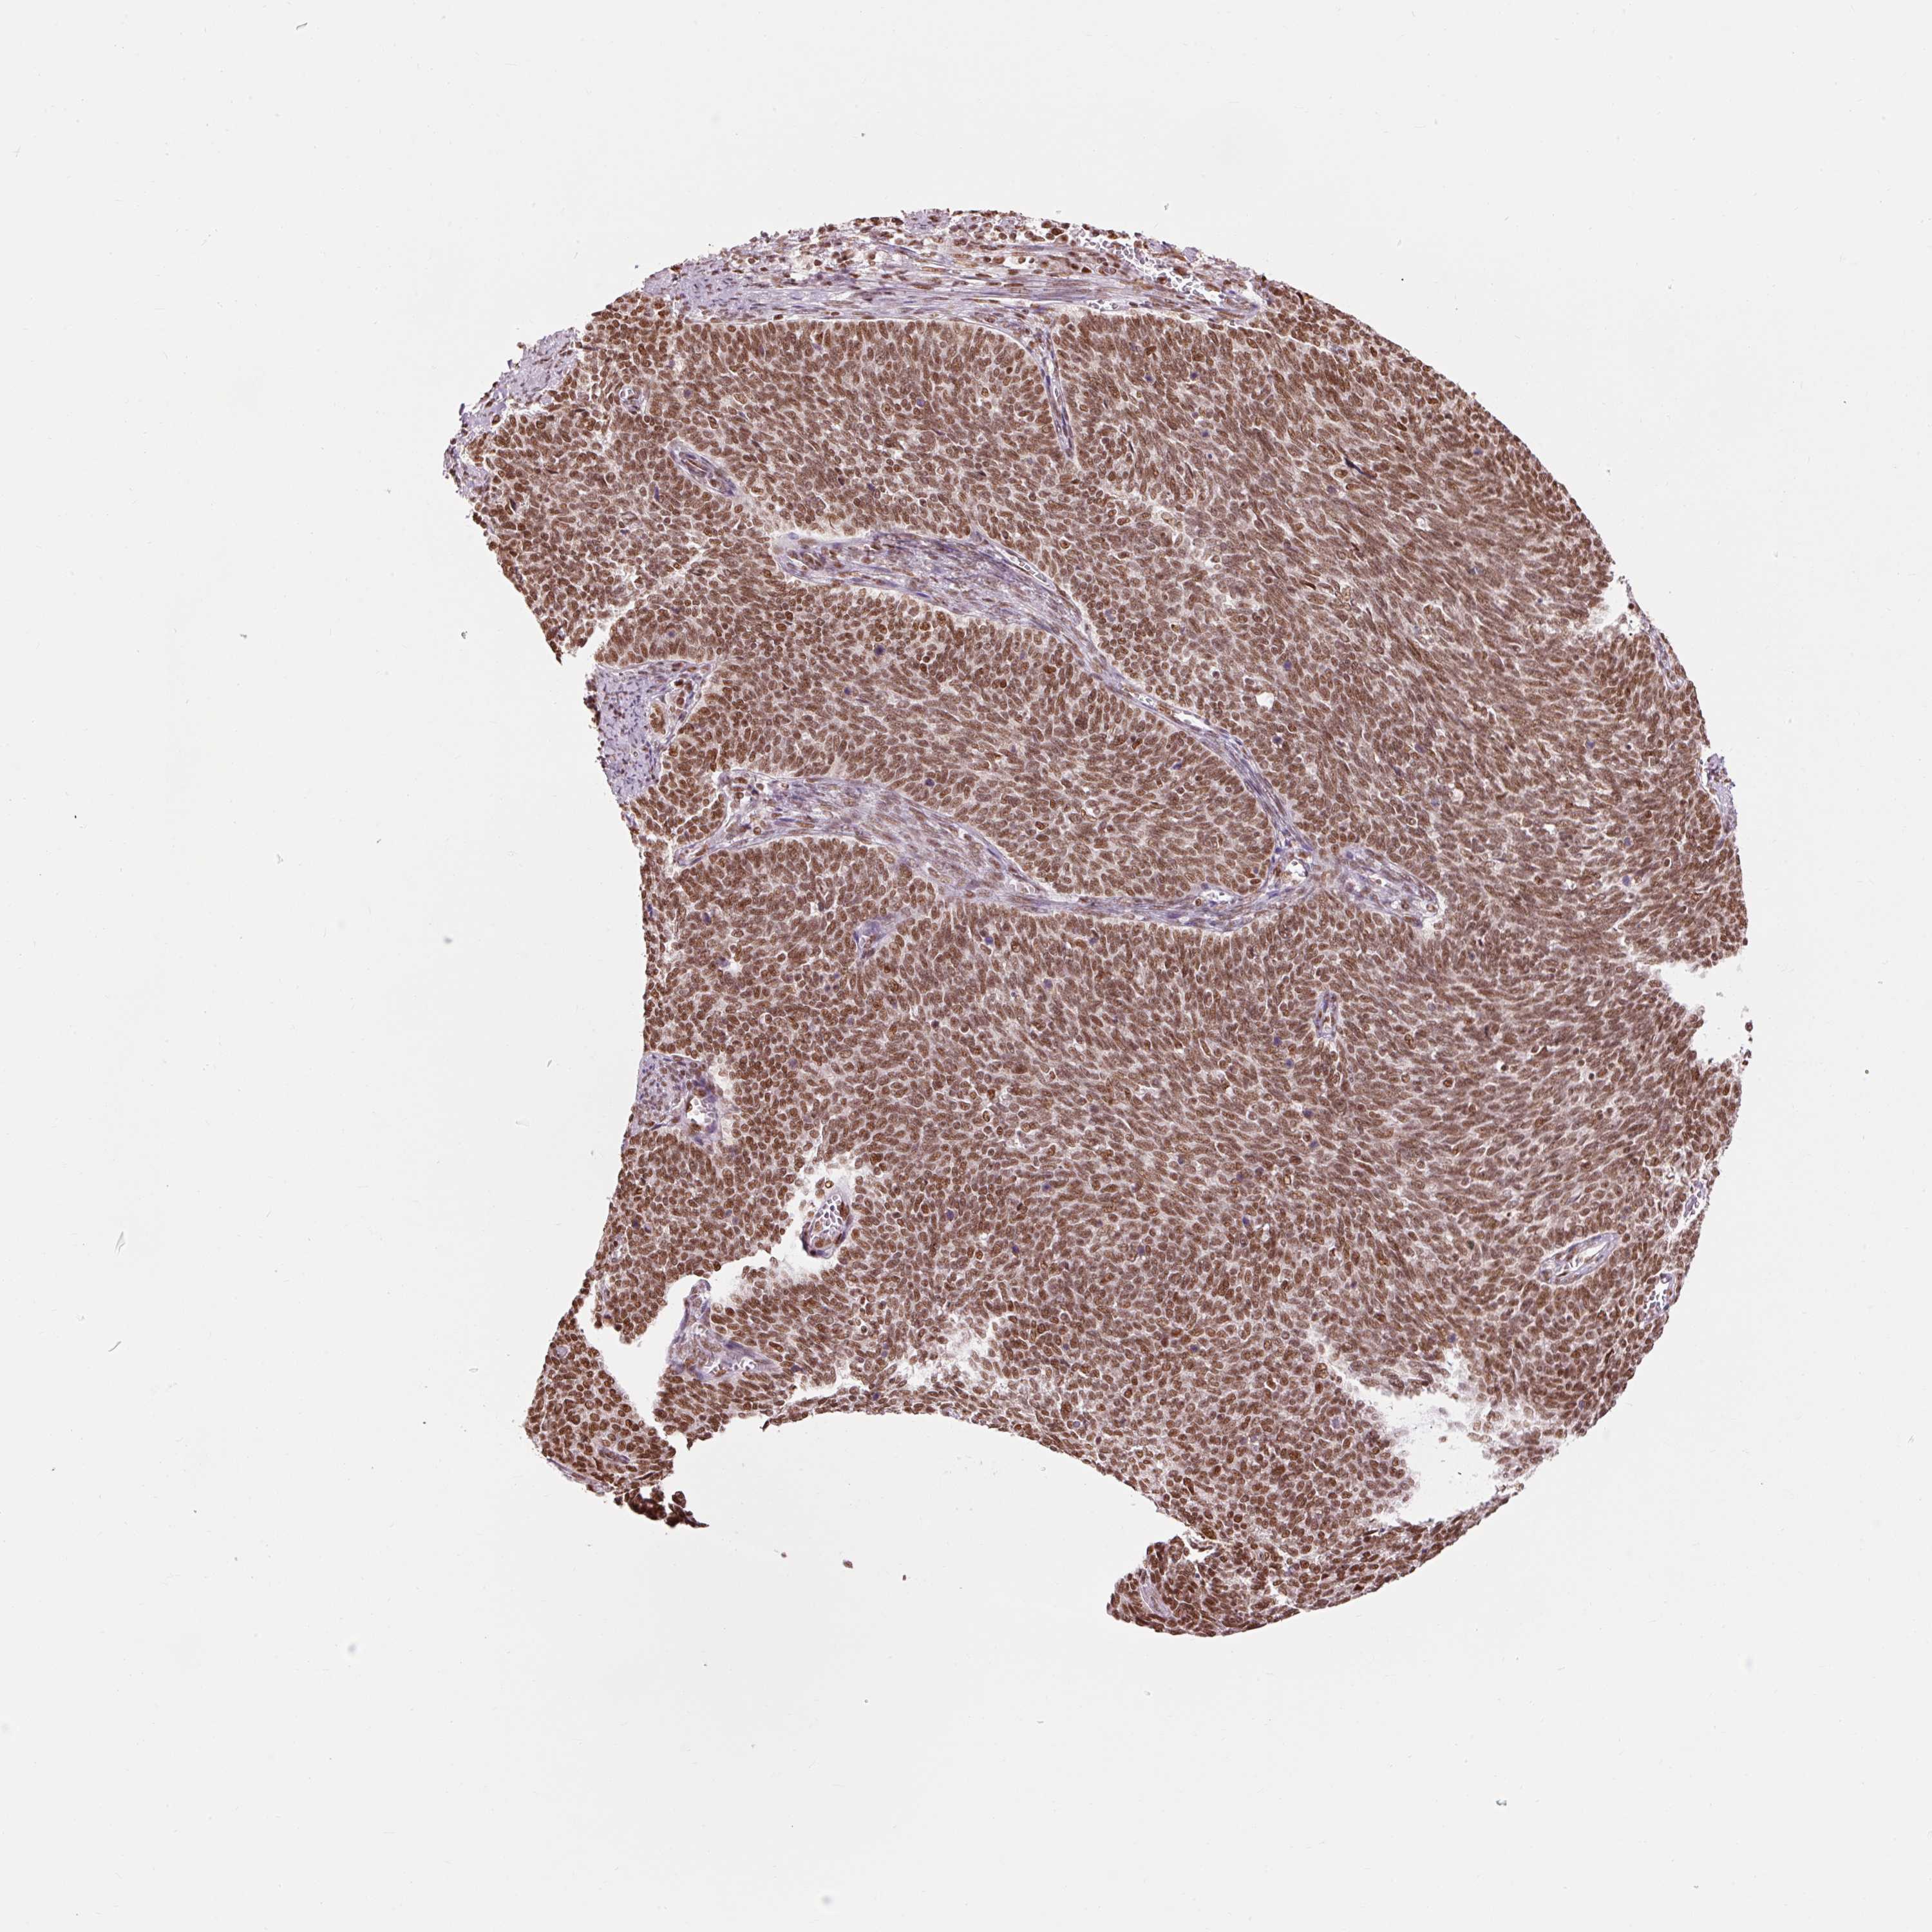

CERVICAL CANCER - Protein expressioni

A mouse-over function shows sample information and annotation data. Click on an image to view it in a full screen mode. Samples can be filtered based on level of antibody staining by selecting one or several of the following categories: high, medium, low and not detected. The assay and annotation is described here.

Note that samples used for immunohistochemistry by the Human Protein Atlas do not correspond to samples in the TCGA dataset.

Antibody stainingi

Antibody staining in the annotated cell types in the current human tissue is reported as not detected, low, medium, or high, based on conventional immunohistochemistry profiling in selected tissues. This score is based on the combination of the staining intensity and fraction of stained cells.

Each image is clickable and will lead to virtual microscopy that enables deeper exploration of all samples and also displays staining intensity scores, fraction scores and subcellular localization as well as patient and tissue information for each sample.

Antibody HPA052589

Staining

High

Medium

Low

Not detected

Intensity

Strong

Moderate

Weak

Negative

Quantity

>75%

75%-25%

<25%

None

Location

Nuclear

Cytoplasmic/membranous

Cytoplasmic/membranous,nuclear

Squamous cell carcinoma, NOS

Adenocarcinoma, NOS